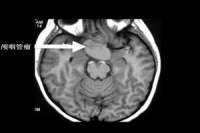

2.CT扫描颅脑CT扫描显示为鞍区肿瘤改变,非增强扫描者实质性肿瘤表现为高密度或等密度影像,钙化斑为高密度,囊性者因瘤内含胆固醇而呈低密度像,CT值为-40~10Hu,囊壁为等密度。病变边界清楚,呈圆形、卵圆形或分叶状,两侧侧脑室司扩大。强化扫描时约2/3的病例可有不同程度的增强,CT值增加12~14Hu,囊性颅咽管瘤呈环状强化或多环状强化而中心低密度区无强化,少数颅咽管瘤不强化。一般具有钙化、囊腔及强化后增强三项表现的鞍区肿瘤。